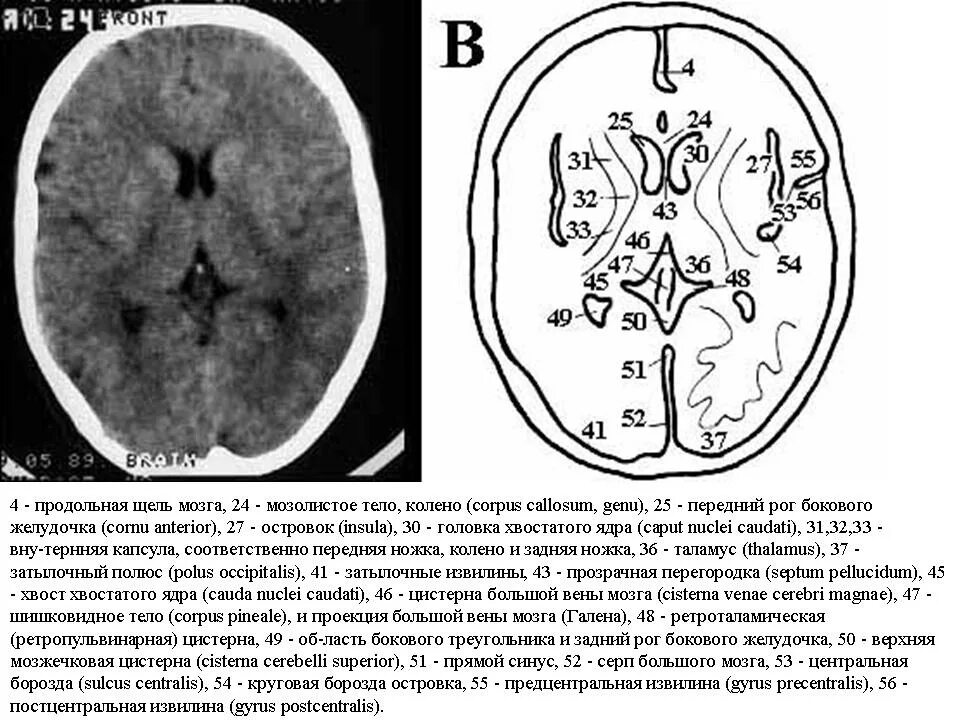

Цистерны на кт